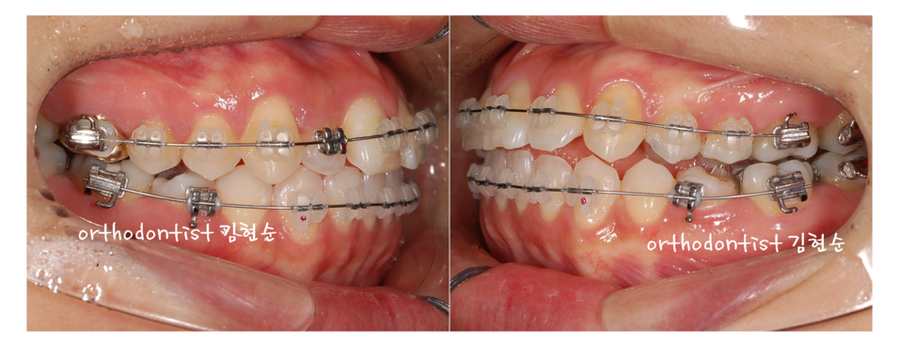

Ⅱ. 세라믹 치과 교정 치료 과정

1

앞서 확인하신 위쪽의

두번째 앞니(측절치)가

들어간 것 외에는

위의 사진처럼

아래치열은

큰 문제는 보이지 않습니다.

하여

- 먼저

3M 사의 글라리티

세라믹 브라켓을 부착,

치아를 뽑지않는

비발치 세라믹 교정을

진행 합니다.

안으로 들어간

두번째 앞니가 문제입니다.

- 두번째 앞니에는

일단 작은 메탈 브라켓을

부착 하였습니다.

- 두번째 앞니가

정상적으로 나오면

세라믹 브라켓을

부착합니다.

앞서 말씀드린 것처럼

비발치로 배열을 하니

치아들이 전체적으로 나와 보입니다.

치아 전체를 안으로

힘껏 끌어당기기 위한

스킬을 추가합니다.

4. 얇은 미니 스크류를

위쪽 치아 뿌리 사이에

설치합니다.

- 위 사진처럼

스프링을 걸어

안으로 끌어당기는 힘을

가중시켜 줍니다.